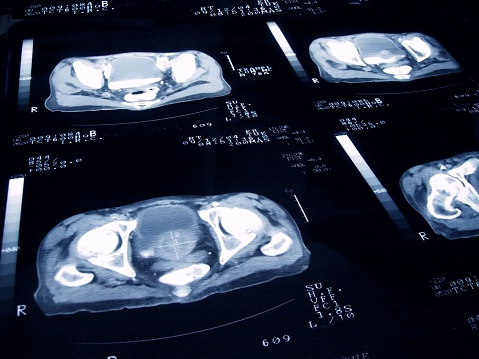

- MRI 및 CT 스캔: 전립선암의 정확한 위치와 확산 여부를 확인하기 위해 사용됩니다.